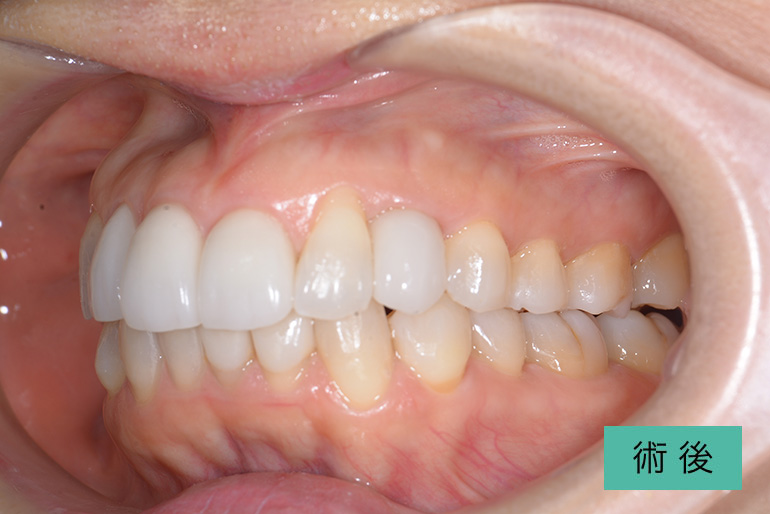

オールセラミック②

| 治療内容 | 上顎前歯右上3番から左上3番のセラミック冠 |

| 治療期間・回数 | 約1ヶ月、3回 |

| 費用(税込) | ¥990,000(165,000/1本)(補綴費用) ※自由診療 |

| リスク・副作用 | 疼痛、補綴物の脱落、咬合違和感、破折 |